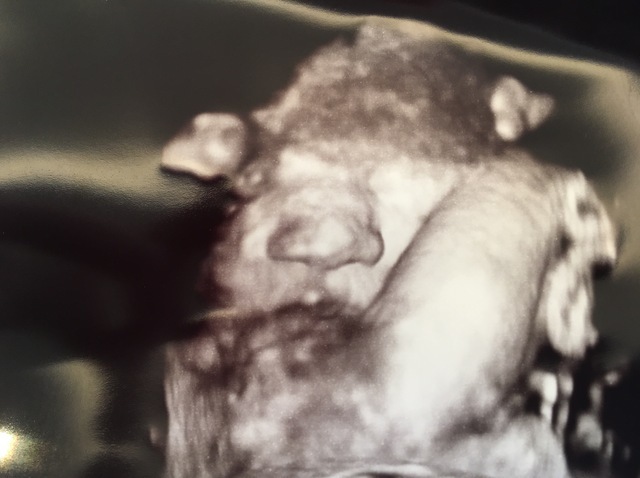

30週6日(30w6d・男の子)|あやたまご♪ さん(25歳)

エコー写真撮影時のエピソード:

初めて4Dエコーを撮った時のエコー写真です。どんな顔かドキドキしながら4Dエコーをした覚えがあります。24週目くらいから4Dエコーを撮っていましたが、1回目は後ろを向いていたので撮れず、2回目は手で顔を隠していたので撮れず…。

3度目の正直でやっとちゃんと顔が見えました。主人に顔がそっくりで笑ってしまったのを覚えています。主人は、そうかな~!?と言っていましたが、本当に似ています(笑)今でも大切な思い出の写真です。